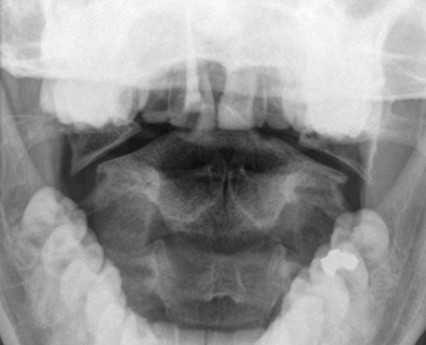

Перелом С1 Джефферсона. Рентгенография через открытый рот. С обеих сторон расширено расстояние от нижних площадок ножек С2 до боковых масс С1. Боковые массы С1 смещены латерально и перестают быть в линию с боковыми массами С1.